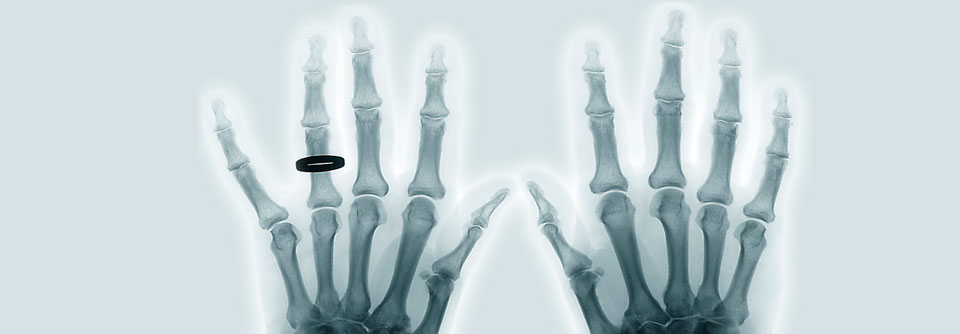

Am häufigsten sind die Knie- und Hüftgelenke betroffen, gefolgt von den Gelenken der Hand. Grundsätzlich können Arthrosen aber in jedem Gelenk auftreten.

• genetische Prädisposition – Heberden-Arthrose der distalen Interphalangealgelenke (DIP) mit Knotenbildung als typisches Beispiel (w : m = 4 :1)